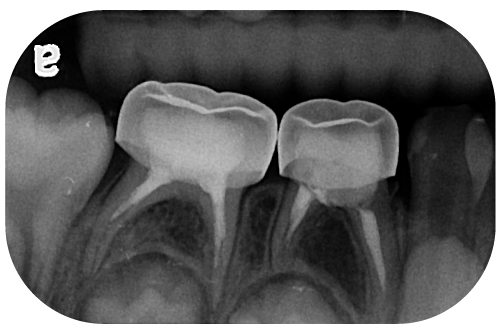

蛀牙已經蔓延至象牙質(牙本質)的 乳臼齒蛀牙

通常這一類型的 乳臼齒蛀牙 會有許多不同的情形,大致可分為口內檢查直接可看到的表面蛀牙,以及藉由 X 光片發現的牙齒鄰接面蛀牙,此時牙齒就需要進一步治療。

治療方式由蛀牙的深度決定,從一般的補牙、搭配活髓保存術或以不鏽鋼牙套保護,避免太脆弱的牙齒斷裂、二度蛀牙等等,端看臨床上牙醫師的評估。